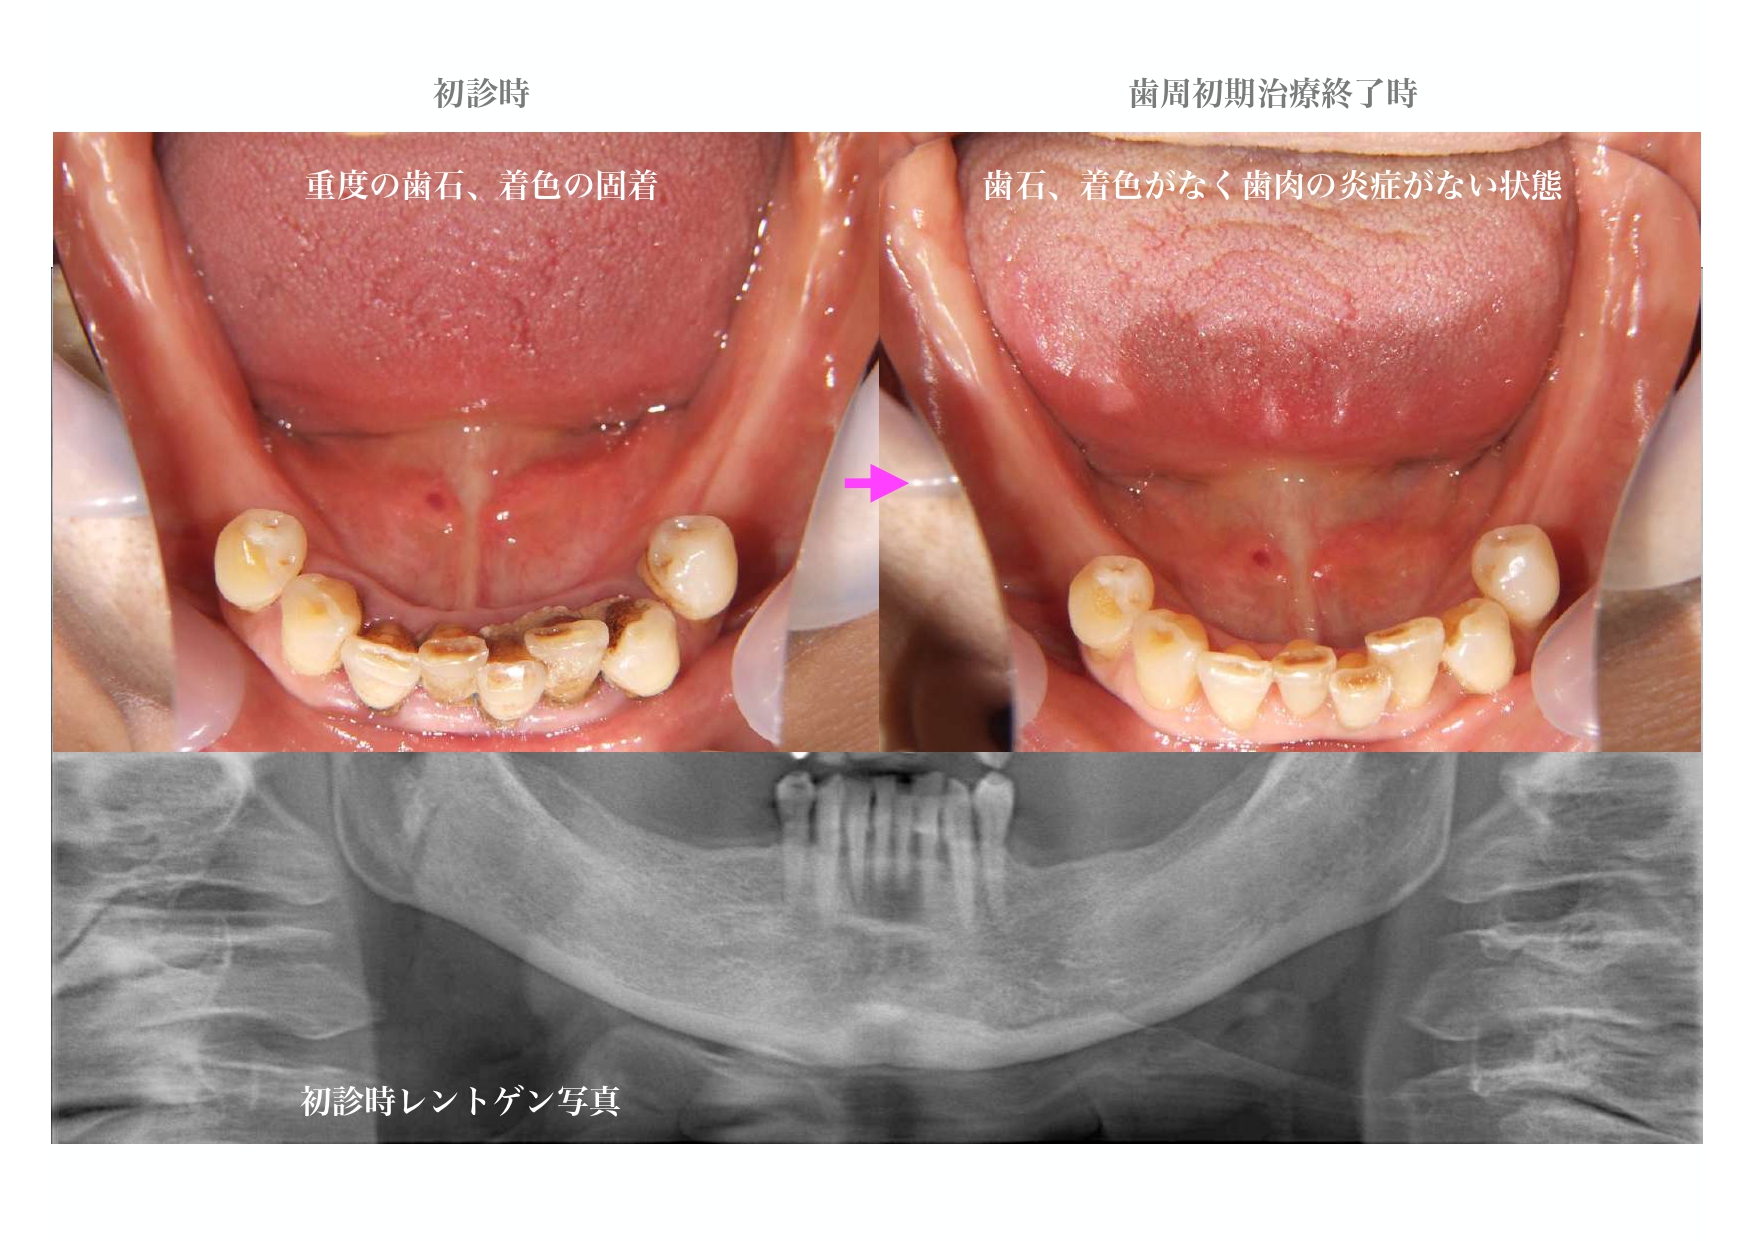

| 主訴 | 義歯が痛い。インプラントで治療してもらいたい。 60代・女性 |

| 治療期間・回数 | 30ヶ月・60回 |

| 治療内容 | 精密検査、コンサルテーション、歯周初期治療、治療用義歯、インプラント4本、GBR、2次手術時歯肉移植、仮歯、部分矯正、上部構造6本、自費コンポジットレジン修復、保定 |

治療詳細